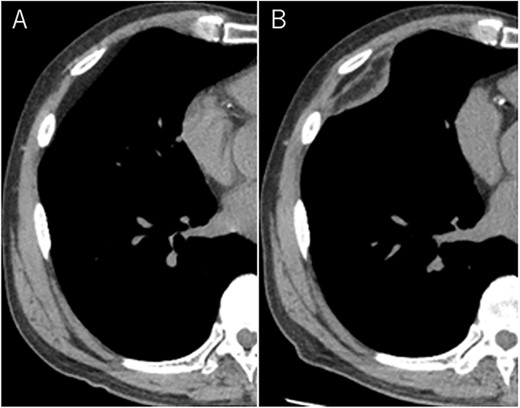

A 72-year-old man with a history of hypertension and left renal cancer (Stage I) was referred to us with a mass in the right chest wall on post-operative follow-up chest computed tomography (CT) for renal cancer. He had a smoking history of 20 pack-years and had no exposure to environmental fumes or dust. Physical examination results were unremarkable. The laboratory findings were within normal limits. Pulmonary function tests and cardiovascular examinations revealed normal results. Chest CT revealed mixed density mass (8.0 × 5.0 × 3.0 cm) located in front of thoracic wall in the third to sixth right intercostal space. The tumor can be revealed as thoracic wall fat (7.8 × 4.8 × 1.2 cm) on CT 1 year before (not considered as abnormal), and it was progressively increased in size and the density changed (Fig. 1A and B). Magnetic resonance imaging (MRI) showed a fatty mass of heterogenic density. T2 high foci (Fig. 2A) and irregular marginal enhancement of the tumor were observed (Fig. 2B). Maximal standard uptake value (SUVmax) of 18F-fluorodeoxyglucose positron emission tomography (FDG-PET) was 3.78 (Fig. 3). Based on these radiological image findings, we scheduled surgery with suspicion of liposarcoma. During the surgery, the patient was placed in the lateral decubitus position. We made 1.5-cm incision in the sixth intercostal space along the posterior axial line for thoracoscopy. We found dense adhesions between the chest wall tumor, lung (front part of all three lobes of the right lung) and diaphragm. We made a 30-cm incision in the fourth intercostal space and resected the tumor along with lung (wedge resection of the front part of all three lobes of the right lung), diaphragm and third to sixth ribs and intercostal muscle. The chest wall defect was 25 × 15 cm and the diaphragm defect was 8 × 5 cm. For reconstruction, the mesh was placed and sutured to the diaphragm and the chest wall. Pathological examination revealed the well-circumscribed tumor with fibrous adhesion between the ribs, lung and diaphragm (Fig. 4A). Microscopically, the tumor consisted of mature fat tissue. There were fat necrosis inflammatory changes in the marginal area of the tumor with foamy macrophages and multinucleated giant cells (Fig. 4B and C). Fluorescence in situ hybridization examination for murine double-minute 2 was negative. Based on these findings, a chest wall lipoma was diagnosed. The post-operative course was uneventful. The patient was followed up for 24 months without evidence of recurrence.

Mixed density mass located in front of thoracic wall; the size was 8.0 × 5.0 × 3.0 cm (B); (A) The tumor seen as thoracic wall fat (7.8 × 4.8 × 1.2 cm) (arrow) on CT 1 year ago; (B) the size increased and the density has changed to heterogenous in 1 year.